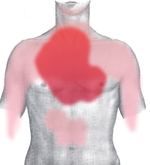

Classical symptoms of acute myocardial infarction include sudden chest pain (typically radiating to the left arm or left side of the neck), shortness of breath, nausea, vomiting, palpitations, sweating, and anxiety (often described as a sense of impending doom). Women may experience less typical symptoms than men, most commonly shortness of breath, weakness, a feeling of indigestion, and fatigue. Approximately one quarter of all myocardial infarctions are silent, without chest pain or other symptoms. A heart attack is a medical emergency, and people experiencing chest pain are advised to alert their emergency medical services, because prompt treatment is beneficial.

The onset of symptoms in myocardial infarction (MI) is usually gradual, over several minutes, and rarely instantaneous. Chest pain is the most common symptom of acute myocardial infarction and is often described as a sensation of tightness, pressure, or squeezing. Chest pain due to ischemia (a lack of blood and hence oxygen supply) of the heart muscle is termed angina pectoris. Pain radiates most often to the left arm, but may also radiate to the lower jaw, neck, right arm, back, and epigastrium, where it may mimic heartburn. Levine's sign, in which the patient localizes his chest pain by clenching his fist over the sternum, has classically been thought to be predictive of cardiac chest pain, although a prospective observational study showed that it had a poor positive predictive value.